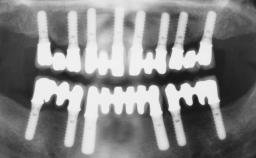

Immediate Loading of Six Implants in the Maxilla and Final Restoration with a Full-Arch CAD/CAM Zirconia FDP

# of Implants 6

Type of Implants One-Piece

Defining Characteristics Fully edentulous upper jaw to be rehabilitated with four or more implants

Modality 6+ implants with immediate loading

Defining Characteristics Fully edentulous upper jaw to be rehabilitated with an implant-borne fixed dental prosthesis